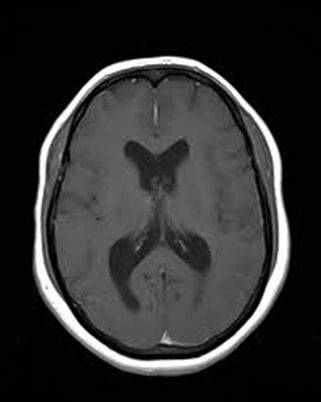

Background: Cavernous hemangiomas are common benign vascular malformations. Their existence in the intraventricular region is very rare. Case Reports: A 43-year old woman with an occipital headache was admitted to the emergency ward. Brain computed tomography scan showed mild hydrocephalus and multiple intraventricular isodense lesions. Imaging findings, especially of Gradient Resonance Echo imaging, were in favor of multiple intraventricular cavernous malformations. Conclusion: This is a rare presentation of multiple cavernous malformation as occipital headache without needing surgical intervention in this phase. Coexistence of periventricular plaques like Radiologically isolated syndrome of Multiple sclerosis is another unique aspect in this report. [GMJ.2017;6(1):61-65]